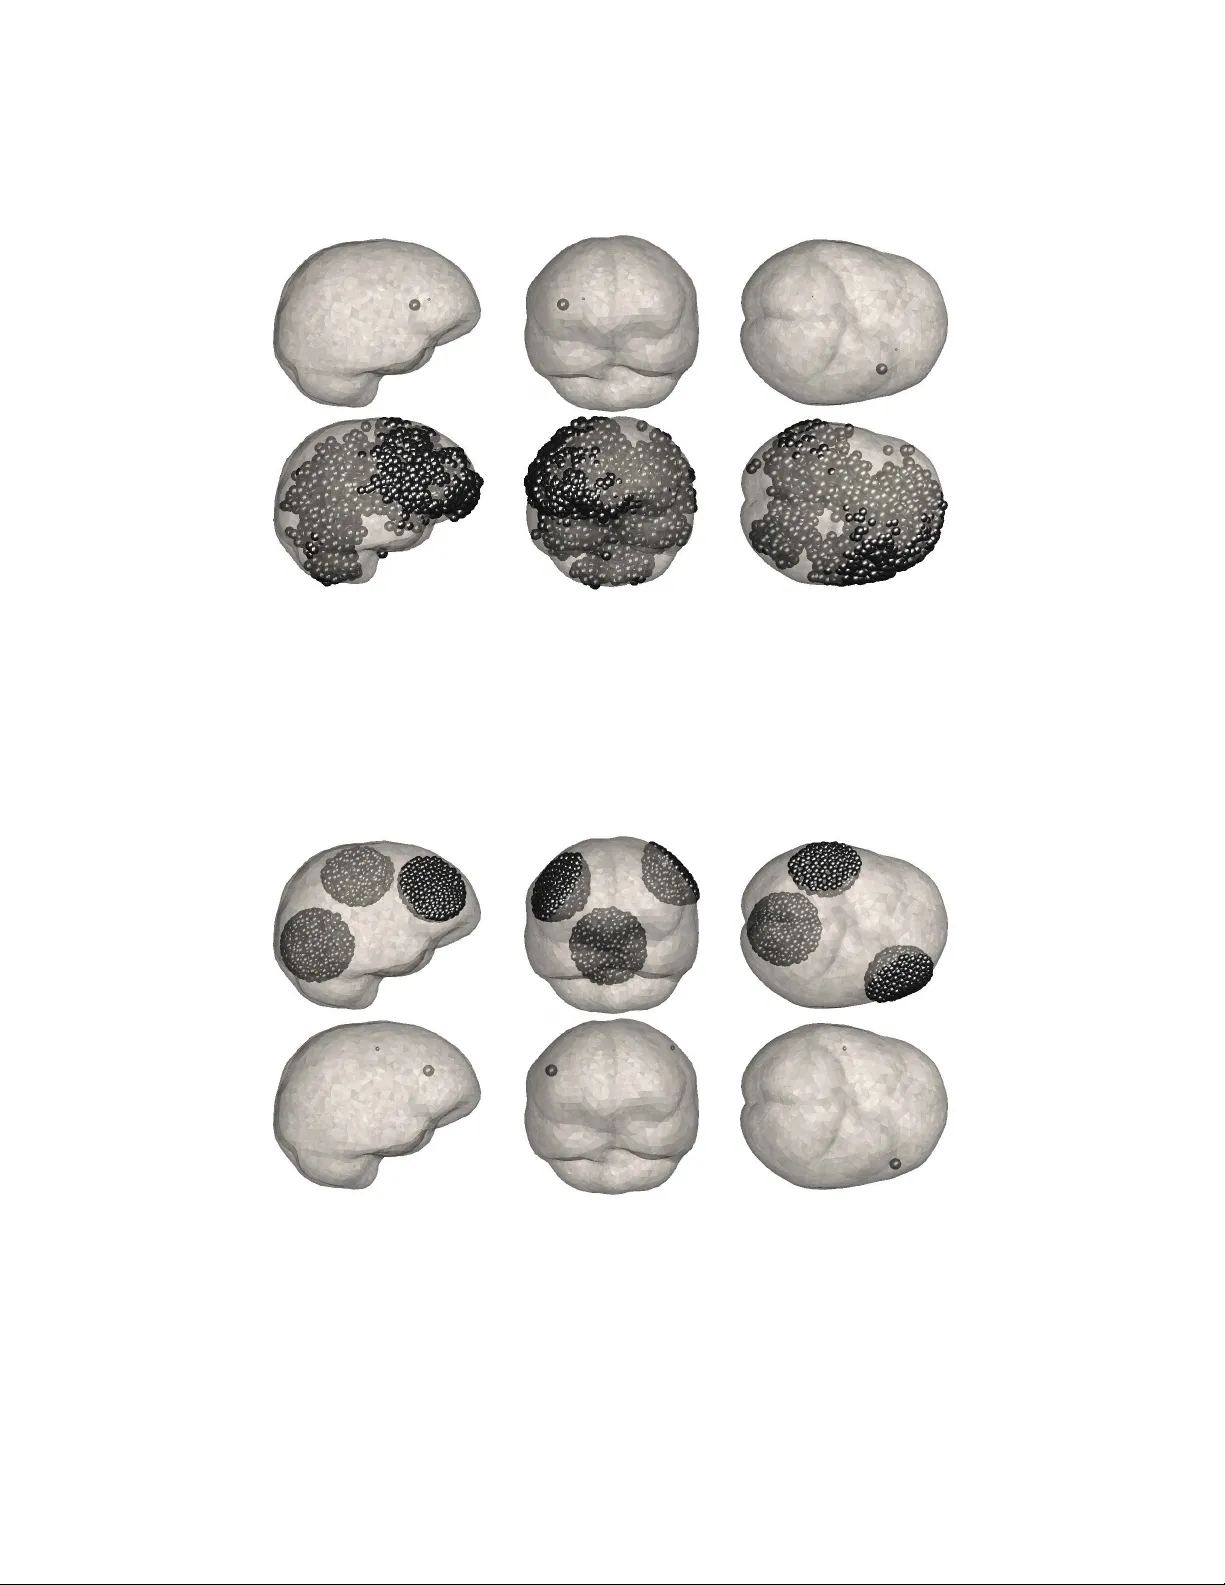

Comments & Academic Discussion

Loading comments...